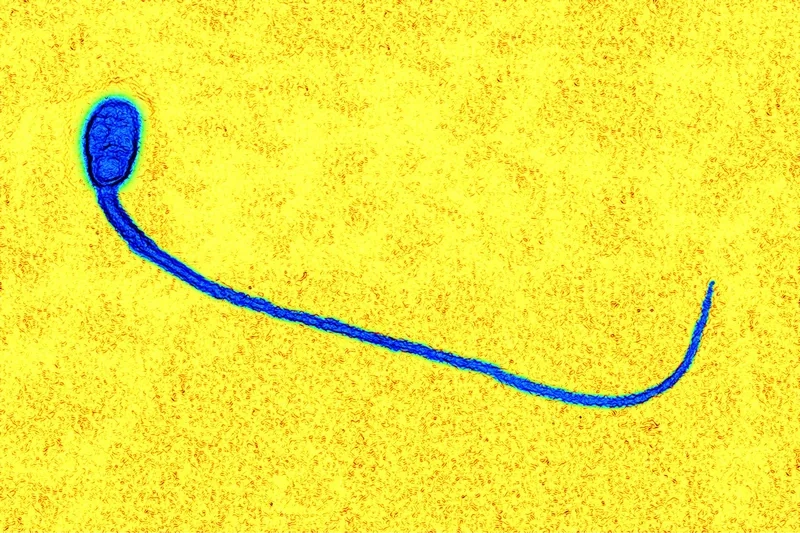

Cấu tạo của tinh trùng dưới kính hiển vi được chia thành ba phần chính: đầu, cổ và đuôi. Phần đầu chứa nhân và enzyme acrosome, cần thiết cho quá trình thụ tinh. Phần đuôi dài và mảnh giúp tạo ra chuyển động để di chuyển về phía trứng.

Chức năng của tinh trùng dưới kính hiển vi là vận chuyển vật chất di truyền của nam giới tới trứng, và tinh trùng di động tốt là yếu tố then chốt quyết định khả năng thụ thai tự nhiên hay trong kỹ thuật tinh trùng ICSI.